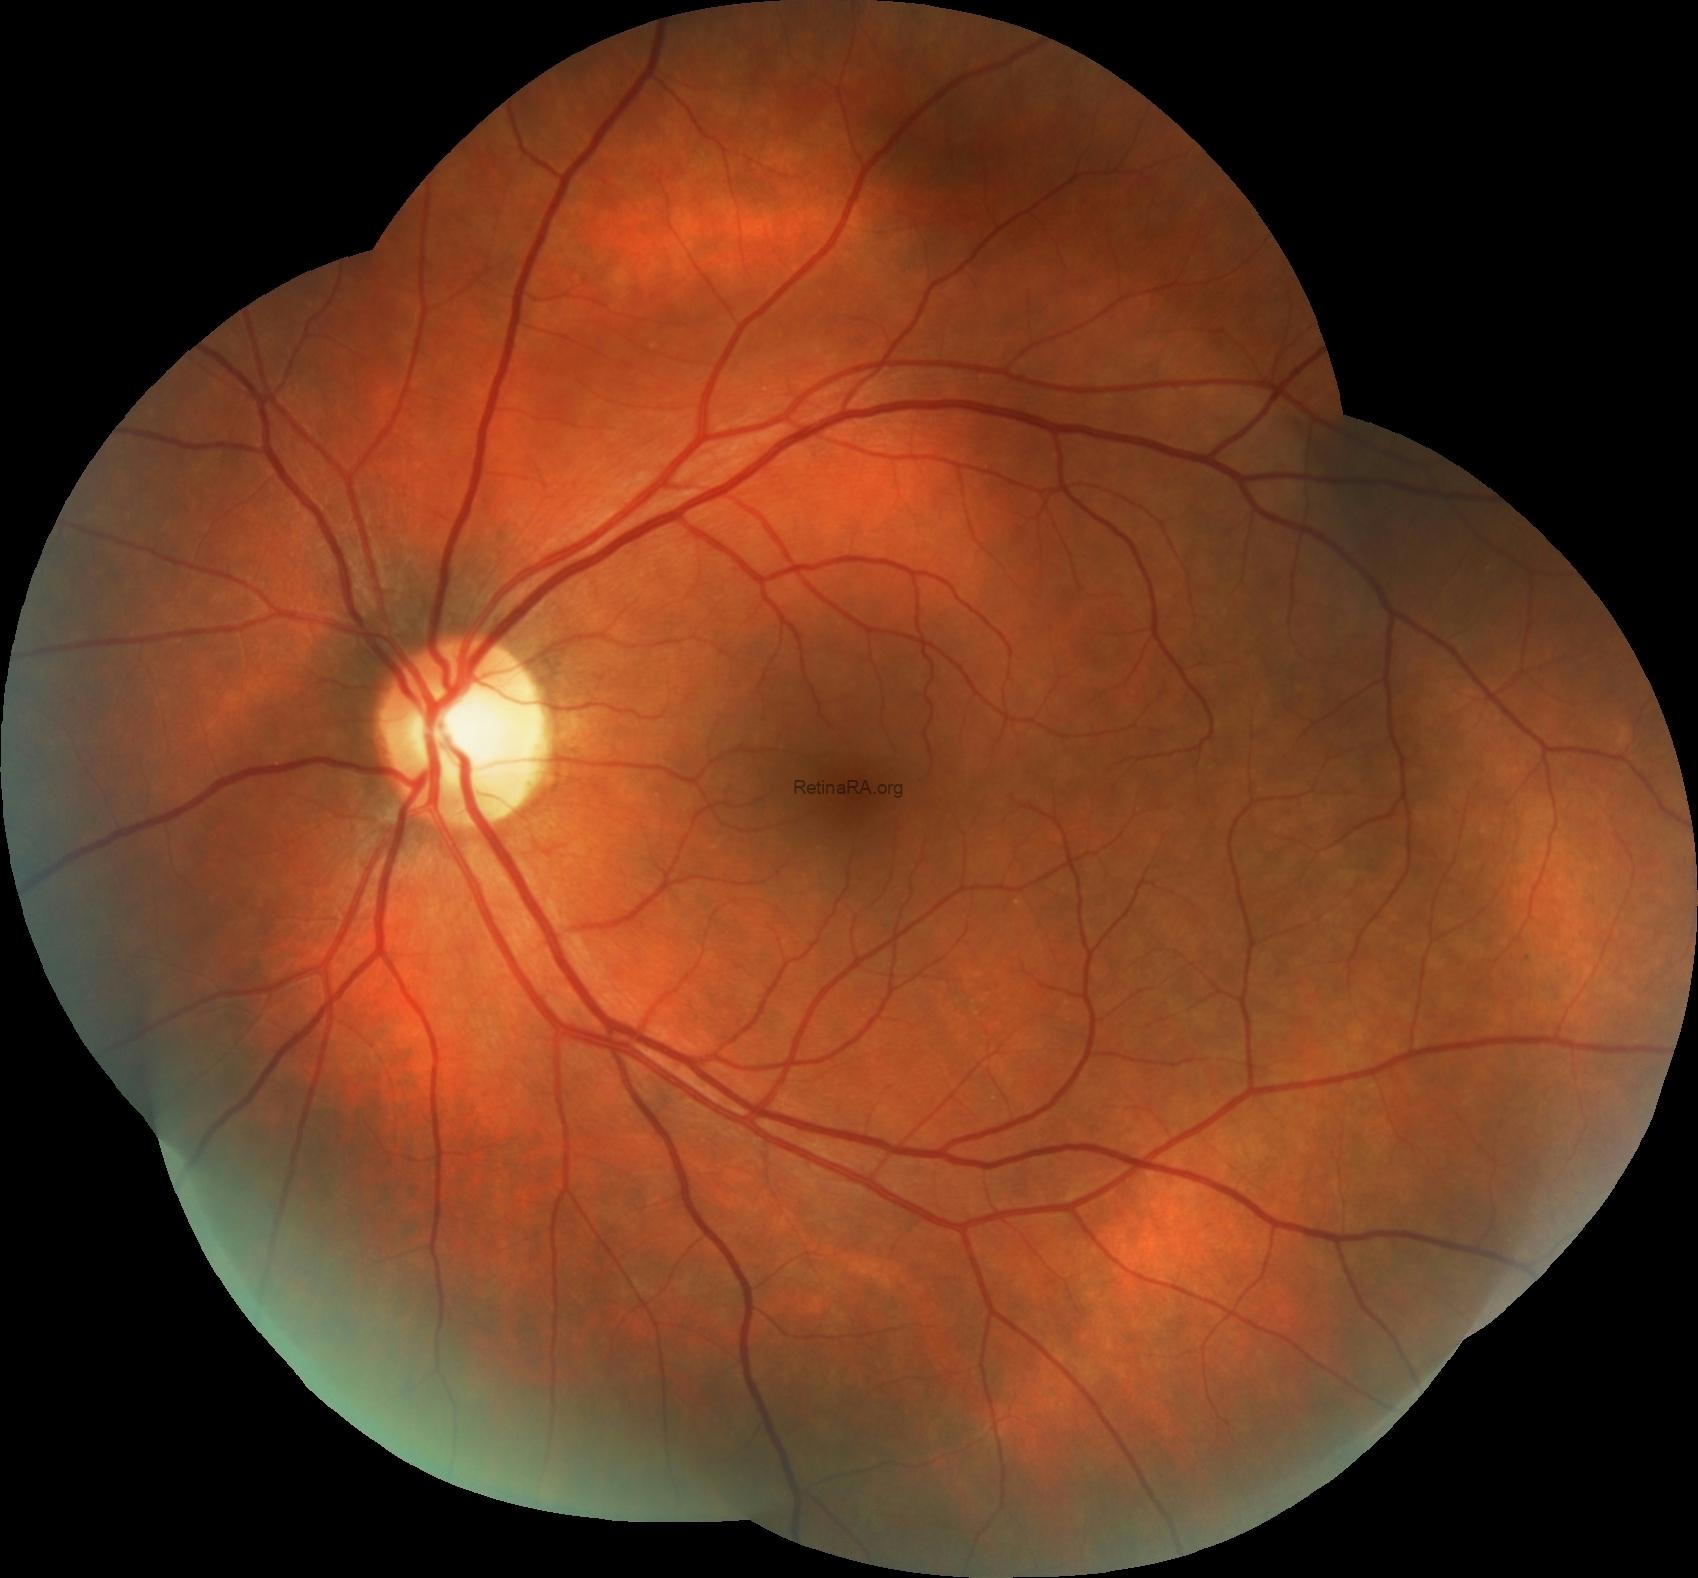

A 45-year-old male patient presented with blurred vision in the right eye. Visual acuity was 0.8/1.0 in right and left eyes, respectively. At the time of presentation, the left eye color fundus photographs show multiple, grayish yellow lesions with unclear borders.